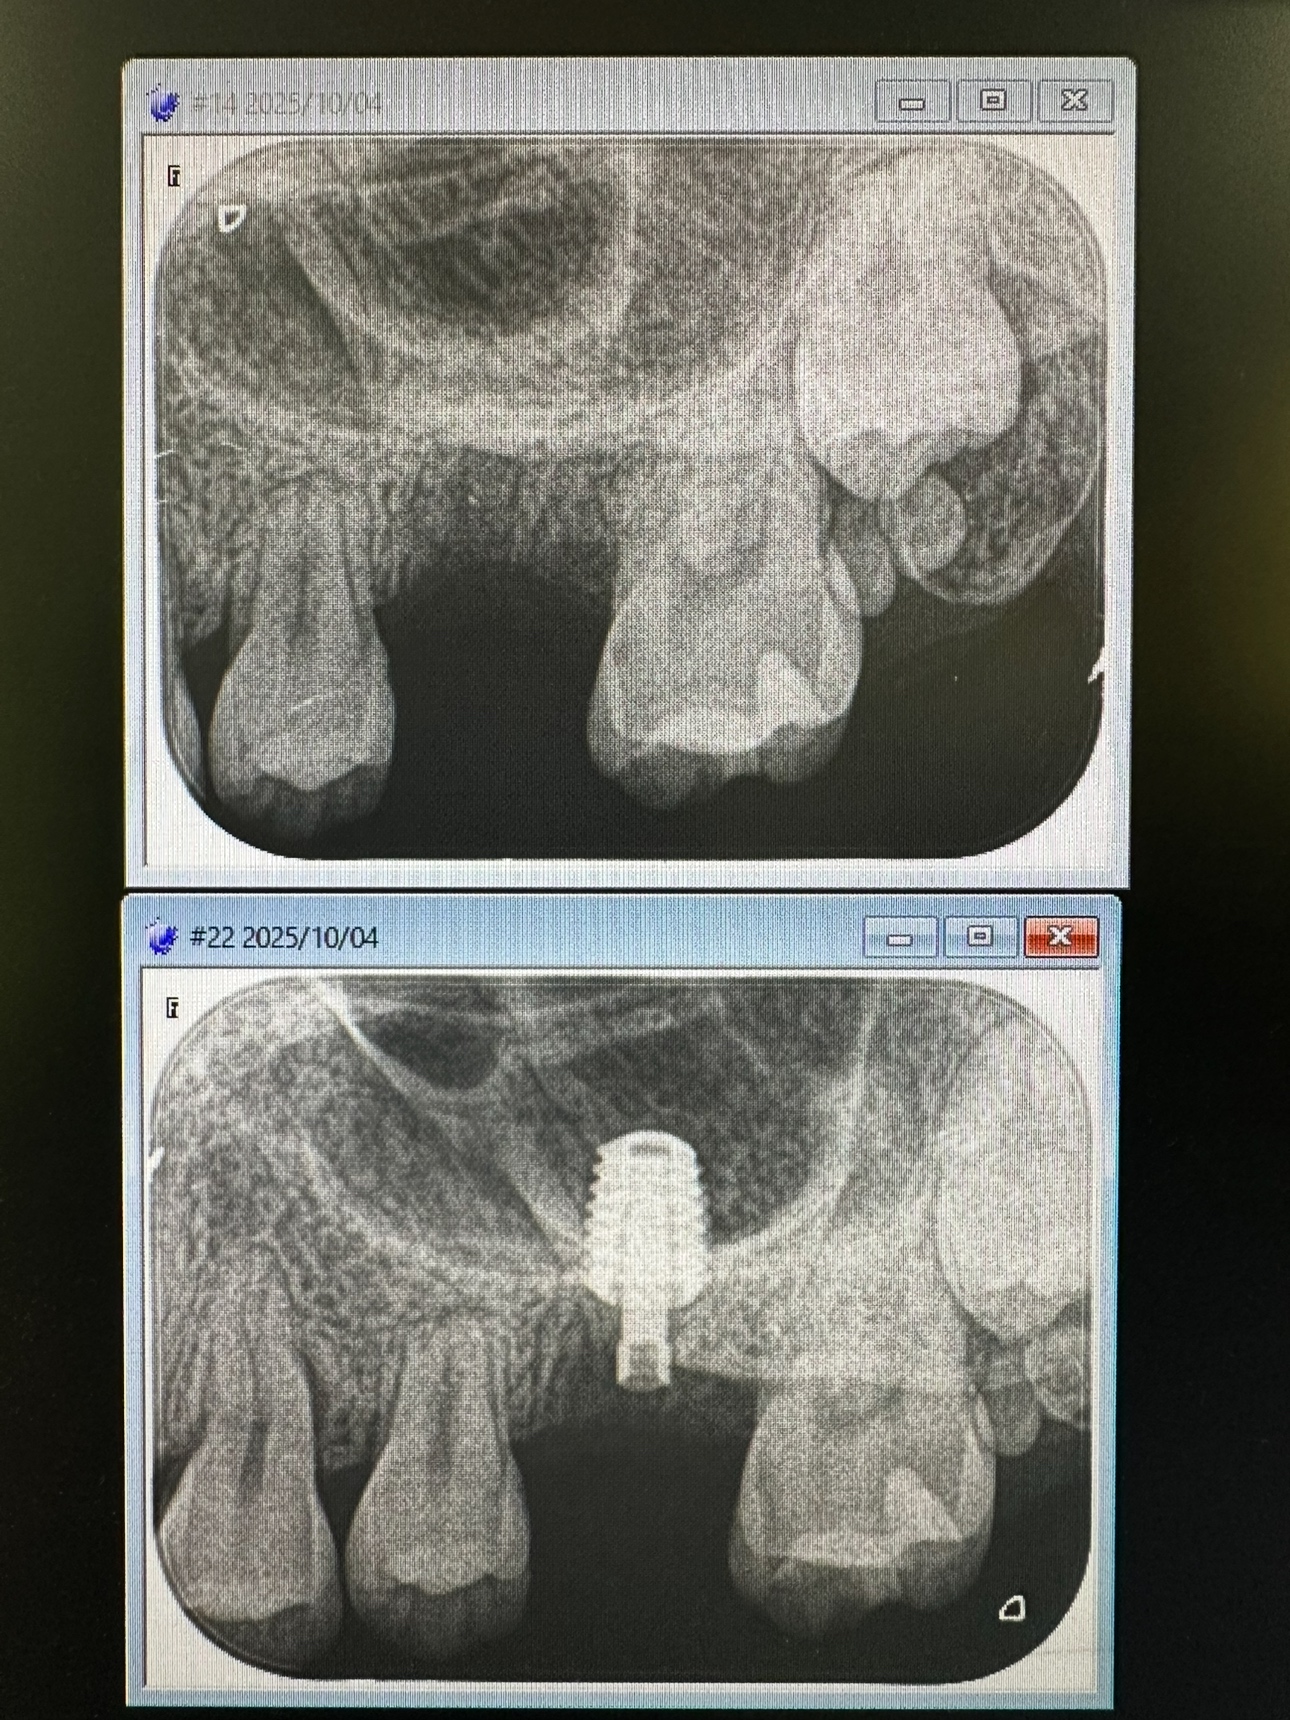

私は、朝からインプラント3本スキャナー印象

昼間からは、危ない動脈近接のソケットリフト

抜歯後2ヶ月待ちオペ、EMDとボナークのお陰です

計測値バッチリ75後半👍👌

6から8wで印象、仮歯かなあ